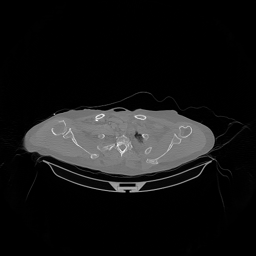

III-D Real Clinical Data Experiment

The experimental results on clinical head data are shown in Fig. 4. The reference images were reconstructed using the fast iterative shrinkage-thresholding algorithm (FISTA) with total variation regularization from non-truncated projection data. In the WCE reconstructions (Fig. 4(b)), severe truncation prevents accurate recovery of anatomical structures outside the FOV. Despite being trained solely on simulated data with a domain gap, all deep learning models can restore a substantial portion of the missing anatomy. Among them, the diffusion-based methods recover soft-tissue boundaries more faithfully than the conventional deep learning approach FBPConvNet, highlighting their stronger image generation capability. However, cDDPM reconstructions exhibit more noticeable noise than those from other methods, consistent with the simulated data results. The patchDiffusion model introduces artifacts within the FOV, likely due to its patch-wise processing strategy. While I2SB shares the same limitations as other diffusion models in perfectly restoring soft-tissue detail, it produces fewer residual noise patterns and fewer artifacts within the FOV boundaries. Overall, Fig. 4 demonstrates the strong efficacy of I2SB in reconstructing real CBCT data.